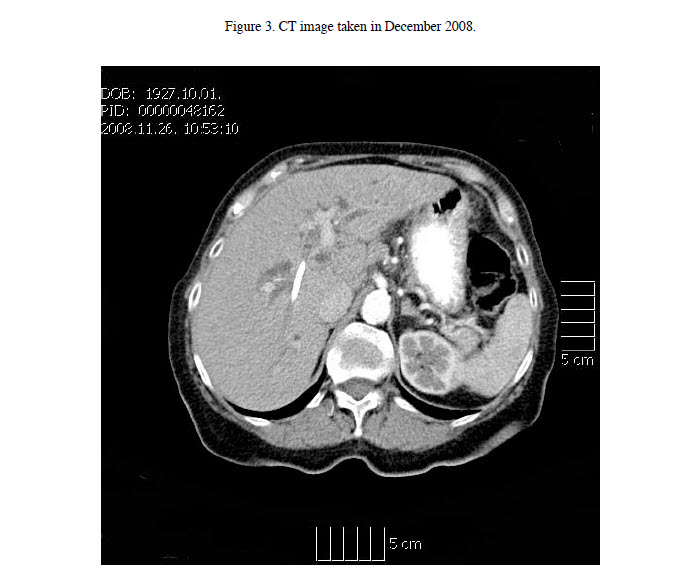

In the middle of November, an abdominal computed tomography scan found no tumor in the abdomen. An image taken in the plane of the porta hepatis is shown (Figure 3).

The next testing in the middle of August 2008 demonstrated a reduction in liver function test markers. Subsequent tests until the end of December 2008 demonstrated somewhat fluctuating liver function test values. A computed tomography scan at the end of November 2008 found no tumor in the abdomen. It is possible that subsequent to tumor resolution, the continuation of elevated enzyme markers demonstrate a phase of this disease that was previously masked by the rapid expiration of patients. Therefore, long- term supplementation of patients could be necessary until enzyme levels return to normal.